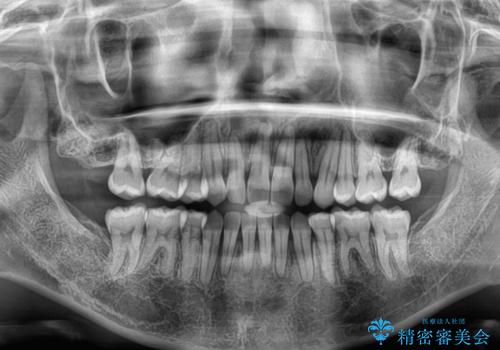

スペースを閉じるために期間を要しましたが、無事に綺麗な口元に仕上げることができました。